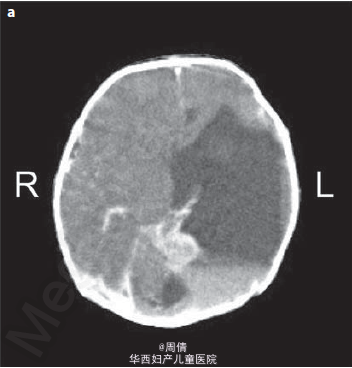

1,2.超声提示在大动脉分叉点以上的降主动脉上有一个动脉瘤,最大直径2cm 3,可见扩大的左脑室和变薄的左侧大脑实质 4,30周时胎儿MRI提示颅腔内的左侧脑室有一个增大的囊性结构

诊断为先天性腹主动脉瘤合并脑穿孔 继续妊娠,孕40周时孕妇产下一个2770g的男婴 体检提示婴儿腹部有一直径2cm的肿块 腹部CT提示降主动脉处有一直径2cm的动脉瘤 脑部CT提示左侧脑室有一囊性结构 出生第三天,MR血管造影提示胎儿期的左颈内动脉阻塞 婴儿6个月时复查腹部CT,提示降主动脉动脉瘤无明显增大,左肾动脉狭窄 因为移植如此小的血管困难太大,所以并未进行手术治疗 但是使用了VP分流器来阻止脑积水的进展